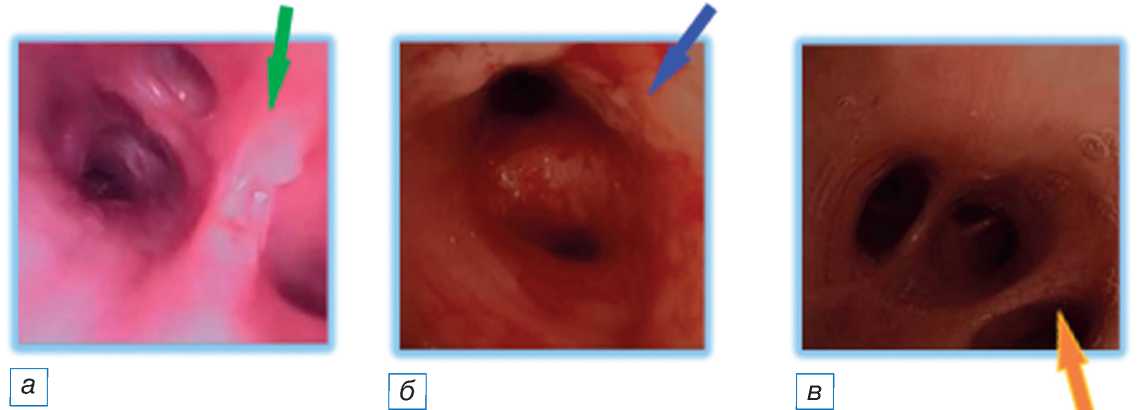

На 3-й день пациенту проведена санационная фибробронхоскопия через трахеостомическую трубку. Под канюлей на слизистой трахеи и частично в просветах главных бронхов обнаружено вязкое гнойное содержимое, слизистая гипереми-рована, сосудистый рисунок смазан, поверхность рыхлая, изменения соответствуют двустороннему диффузному атрофическому эндобронхиту II степени (рис. 2). При последующей визуализации лёгочной ткани вентиляция становится более равномерной, выявлена ключевая зона гиповентиляции в дорсальных отделах правого лёгкого, отмечается коррекция центра вентиляции (рис. 3).

Рис. 2. Состояние бронхиального дерева после санации. Этапы визуализации (стрелками указаны патологически изменённые участки): отёк межбронхиальной перегородки ( а ); гиперемия стенок бронхов 2–3-го порядка ( б ); удалённая мокрота просветов бронхов 4-го порядка ( в ).